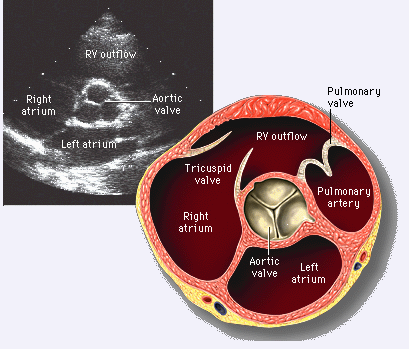

(图) 心底短轴切面 (二维超声心动图)

图片尺寸944x727

经典心脏超声切面图及解剖解释

图片尺寸893x584